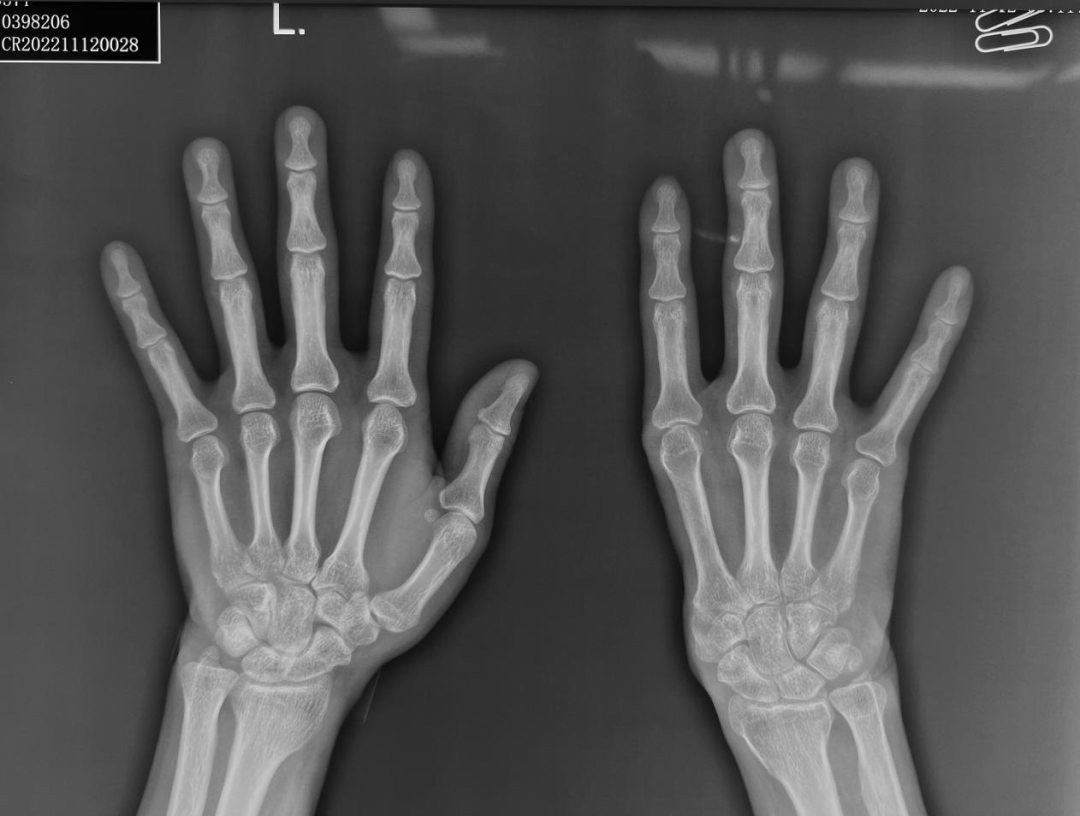

来自河北的张先生(化名)就是重度拇指缺损的患者。张先生在工作时右手拇指不慎被机器挤压,导致严重的开放性创伤,拇指仅有一小条皮蒂与手掌相连,当地医院急诊就诊后,医生经探查拇指情况,发现组织毁损严重,没有再植条件,只好去除毁损的拇指,把伤口清创缝合。伤口顺利愈合了,但生活的打击才刚刚开始。由于创伤范围大,伤后拇指及第一掌骨、大鱼际软组织均完全缺损,整个手掌仅剩下四个掌骨及四个手指,右手的功能受到严重影响,劳动能力严重下降。对于正值壮年的张先生来说,作为家庭的顶梁柱,上有老下有小,挣钱养家是理所当然的责任,但右手功能的缺损却让他无能为力。经过一段时间的迷茫与挣扎,在爱人的劝导下,“现在的医学技术这么发达,一定有办法重新造出一个大拇指来的”,夫妻二人决定踏上求医之路。经过多方就医、筛寻、比对,张先生终于接触到了一个与他类似的病例——去年3月,北京积水潭医院陈山林团队曾完成了世界首例3D打印技术辅助下再造拇指全长缺损,张先生抱着最后的希望来到积水潭医院。经多次咨询和问诊,张先生最终确定治疗方向。陈山林团队接诊后,经过检查,发现张先生拇指完全缺损,大鱼际部分完全缺损,自大多角骨以远骨关节完全缺损,在分型上属于六度缺损,几乎是最重度的分型了。张先生坚决拒绝从髂骨取骨等其它传统方案,要求利用3D打印技术为他打印掌骨和关节。结合患者要求,经治疗组讨论,陈山林团队决定利用3D打印技术自体结合组织游离移植技术再造第一掌骨系列。

3D打印技术再造拇指并不是直接打印出一个拇指移植到手上,目前医学还无法达到这一步。这个技术的本质,是将双侧手的影像资料数字化,利用电脑软件将伤侧手缺损的部分在健侧手上标记出来,再通过镜影技术将再造所需的部分生成患侧的形状,用3D打印机打印出金属假体,再与自身组织移植结合,从而再造出所需要的人体部位。对于这个患者,需要打印的成分是第一腕掌关节及第一掌骨。